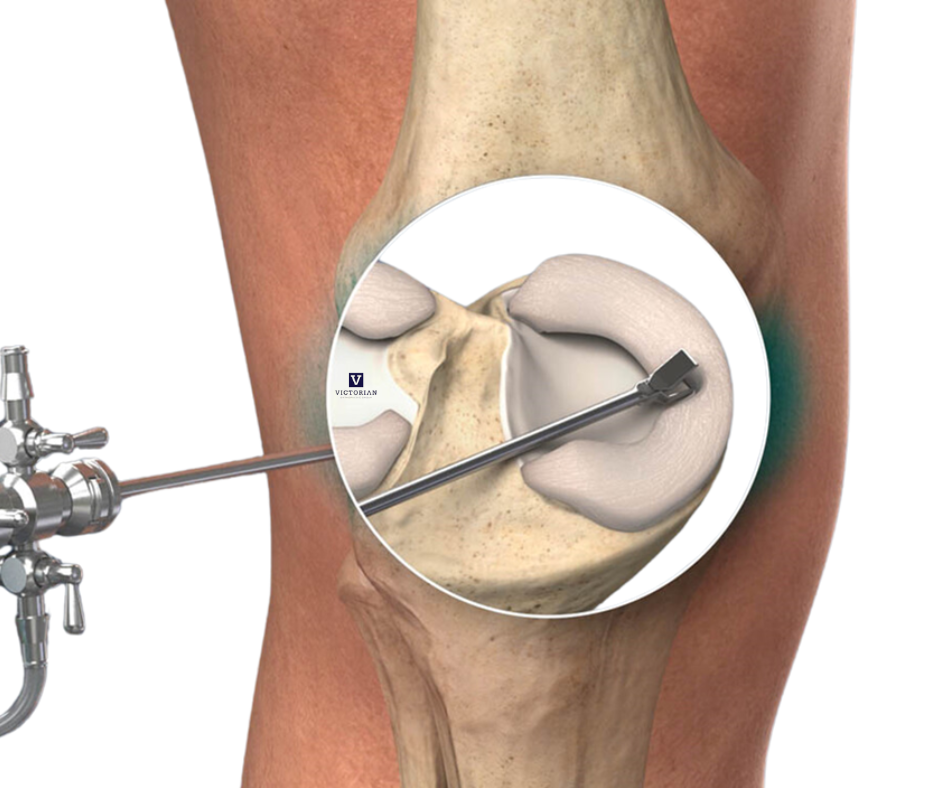

Knee Arthroscopy